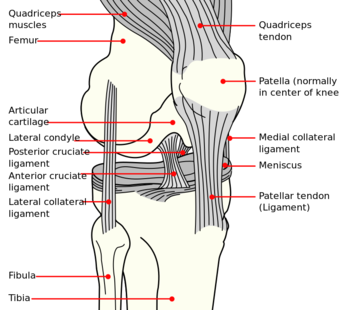

رسم تخطيطي لرباط الركبة. | |